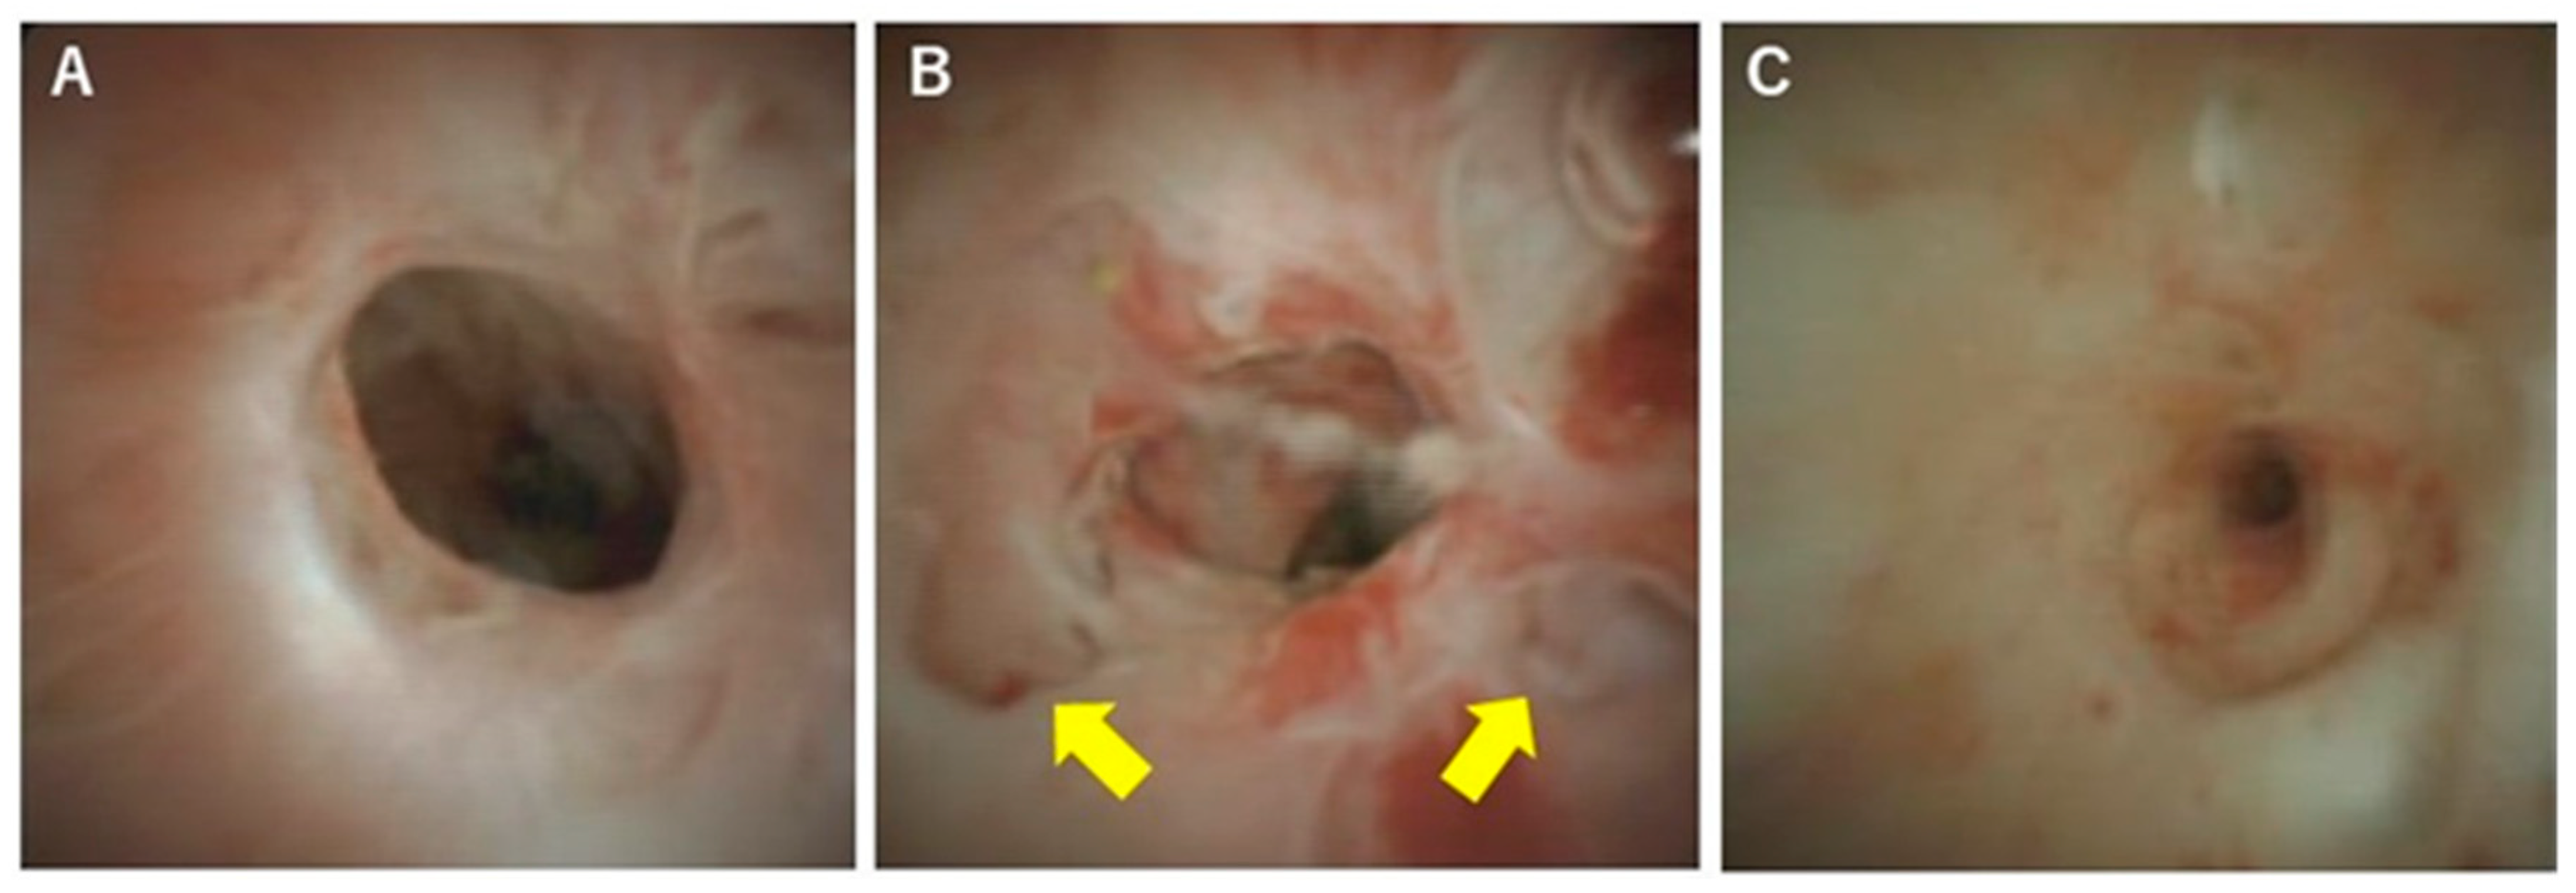

In terms of differentiation by appearance, Itoi et al. examined the usefulness of cholangiography for differentiating PSC, IgG4-SC, and cholangiocarcinoma [32]. They classified cholangioscopic findings into the following nine features: (1) mass formation, (2) bile duct stenosis, (3) dilated vessels, (4) tortuous vessels, (5) partially enlarged vessels, (6) irregular surface, (7) scarring, (8) pseudodiverticula, and (9) friability. As a result, scarring and pseudodiverticula were found to be characteristic findings of PSC, and partially enlarged vessels were characteristic of cholangiocarcinoma. The other findings of mass formation, dilated vessels, tortuous vessels, irregular surface, and friability were observed in both IgG4-SC and cholangiocarcinoma and were not helpful for distinguishing the two diseases. An irregular surface, although rare, was also observed in PSC. Sandha et al. further investigated the cholangioscopic findings of PSC and stratified PSC into the following three types based on visual characteristics: (1) inflammatory, (2) fibrostenotic, and (3) nodular or mass-forming. The inflammatory type showed mucosal erythema, ulceration, and fibrinous white exudate; the fibrostenotic type showed circumferential rings and asymmetric cicatrization; and the nodular or mass-forming type showed focal nodular tissue growth [33]. Although the small numbers of patients in both studies (five [32] and 29 [33] patients) might not accurately represent the overall disease characteristics of PSC, these results suggest that the cholangioscopic findings of PSC may vary according to the disease stage. Itoi et al. proposed that scarring and pseudodiverticula might only be indicative of the fibrostenotic type of PSC. The presence of the nodular or mass-forming type should signal the possibility of cholangiocarcinoma. We also experienced cholangiography in our PSC patients, and all of the findings, except partially enlarged vessels, were observed. Mucosal erythema (Figure 3A), ulceration (Figure 3B), fibrinous white exudate (Figure 3C), and irregular surface (Figure 3D) are often observed in active-phase patients with repeat acute cholangitis. These findings appear during the relatively early stages of PSC and might be classified as the inflammatory type, as proposed by Sandha et al. Patients with this type of PSC are also likely to have dilated vessels (Figure 4A), tortuous vessels (Figure 4B), friability (Figure 4C), and mass formation (Figure 4D). However, these findings are commonly observed in cholangiocarcinoma cases. On the other hand, scarring (Figure 5A), pseudodiverticula (Figure 5B), and bile duct stenosis (Figure 5C) are often observed in chronic-phase patients with a long history of PSC. Such patients might be classified as the fibrostenotic type. The finding of mass formation is sometimes observed in both the active and chronic phases of PSC. Since mass formation is difficult to distinguish from cholangiocarcinoma, it should be noted regardless of the phase. The time course of each phase and the characteristics of the different PSC types according to phase are summarized in Figure 6.

Figure 5. Cholangioscopic findings characteristic of the chronic phase of PSC. (A) Scarring, (B) pseudodiverticula (yellow arrows), and (C) bile duct stenosis. These findings are observed mainly during the chronic phase of PSC.